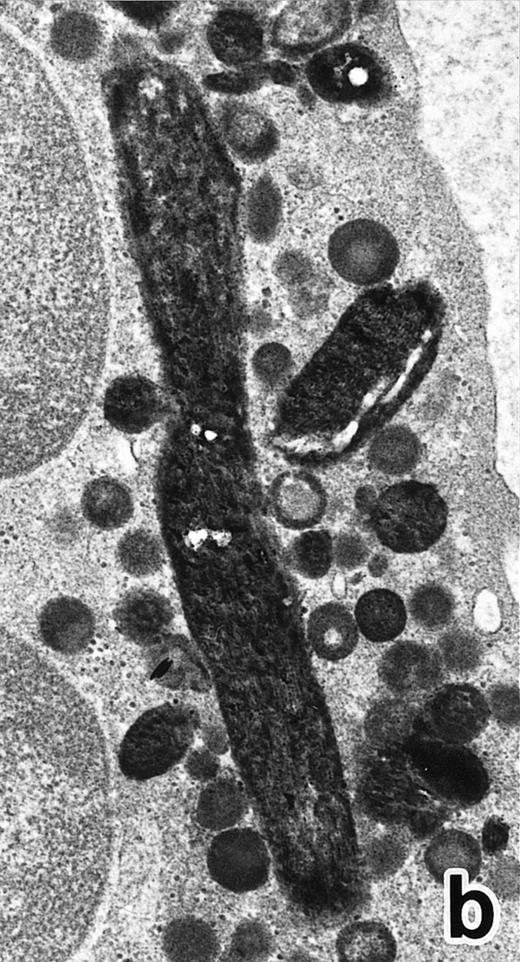

Common morphological changes of bone marrow leukemia cells were observed during ATRA treatment. After 1 week of ATRA treatment, leukemic cells showed heterochromatin condensation and nuclear lobulation (Figs 3 and 4). Although the lobulated nuclei of some cells resembled those of PMNs, these nuclei were irregular in shape and nucleoli were occasionally present. The lobulated nuclei often had nuclear blebs (Fig 3a) or were connected by thin nuclear material (Fig 4a), called filamentous connections,13 that consisted of heterochromatin delimited by the nuclear membrane. In addition to these changes, the irregularly shaped primary granules became morphologically normal. This was most evident in patient no. 1, in whom the majority of both Auer rods and irregularly shaped inclusions, as shown in Fig 2, dramatically vanished and the remaining primary granules appeared normal, being spherical in shape and relatively homogeneous in size (Fig 3a), although abnormal primary granules and/or Auer rods were infrequently observed in some cells. Rarely, a structure composed of an Auer rod coupled with a primary granule was found, appearing as though the seemingly normal primary granule had emerged from the Auer rod (Fig 3b). Type I primary granules still predominated in all patients, but type II primary granules with a nucleoid structure were rarely observed in patients no. 1 and 2. Some maturing neutrophils with abnormally shaped lobulated nuclei in patient no. 2 possessed unusual, possibly immature, primary granules containing central electron-dense material (Fig 4a and b), indicating asynchronous maturation of nuclei and cytoplasmic granules.

(a) A PMN in patient no. 2 after 10 days of ATRA treatment. The nuclei are irregularly lobulated, with some of them being connected by nuclear filamentous structures, and heterochromatin is condensed along the nuclear membrane. (Original magnification × 13,100.) (b) Higher magnification of a portion of the cell in (a). The cytoplasmic granules are large and spherical, and some of them contain flocculent material and central cores with higher electron density. (Original magnification × 20,200.)